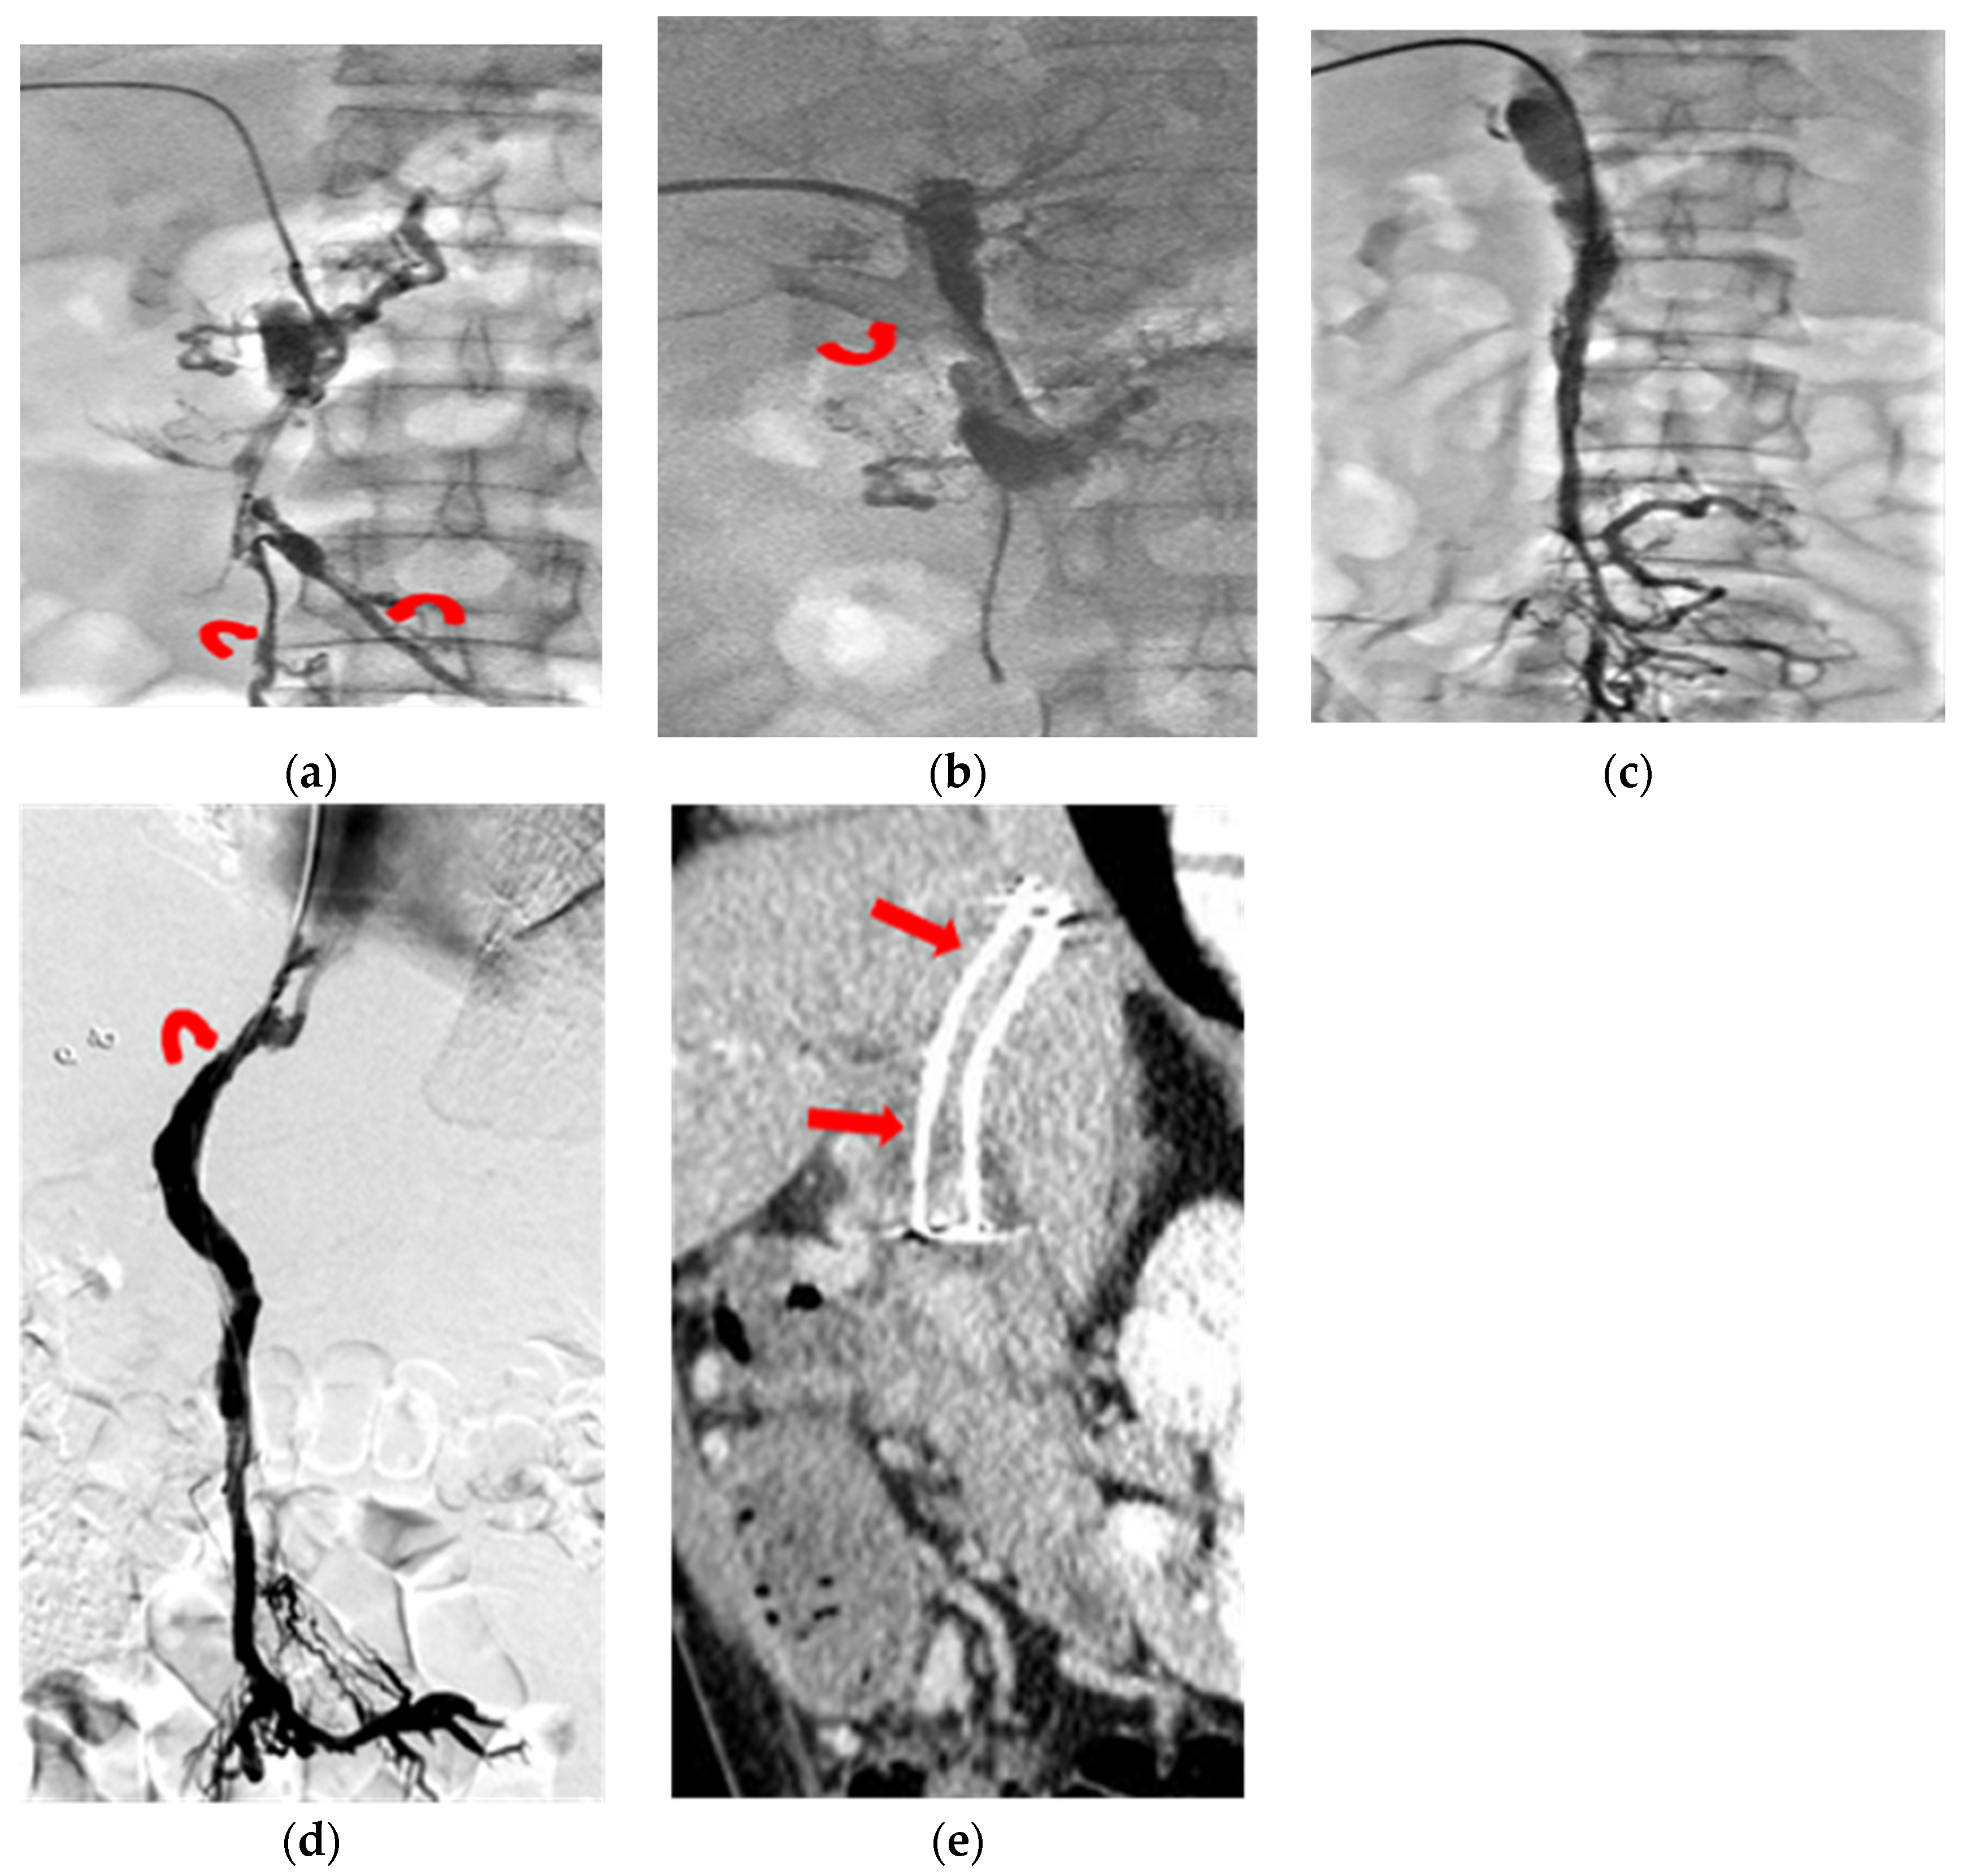

2. Patients and Methods

3. Thrombolysis Technique